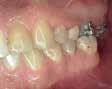

- Short head Mini-screw 1.6 diameter, 8 mm length Titanium alloy (Absoanchor®) palced between the mandibular first Premolar and canine at the junction between attached and movable mucosa in a 45 degrees inclination.

- Lower wire: 16x25 stainless steel wire

- Connecting first molar hook to the micro-implant with a chain generating about 200g of force

- To avoid irritation of the cheek when in contact with the miniscrew head, a light cure silicone material was applied to cover the chain and the mini-screw all-together (Softflow®).

For almost 8 months, during the Covid pandemic, the patient was unable to present to the clinic. The work was resumed in March 2022. It was decided then to segment the appliance, including third molar to canine. The 16x25 SS wire was replaced with 17X25 S.S in the lower arch to increase the rigidity of the wire given the short span available.